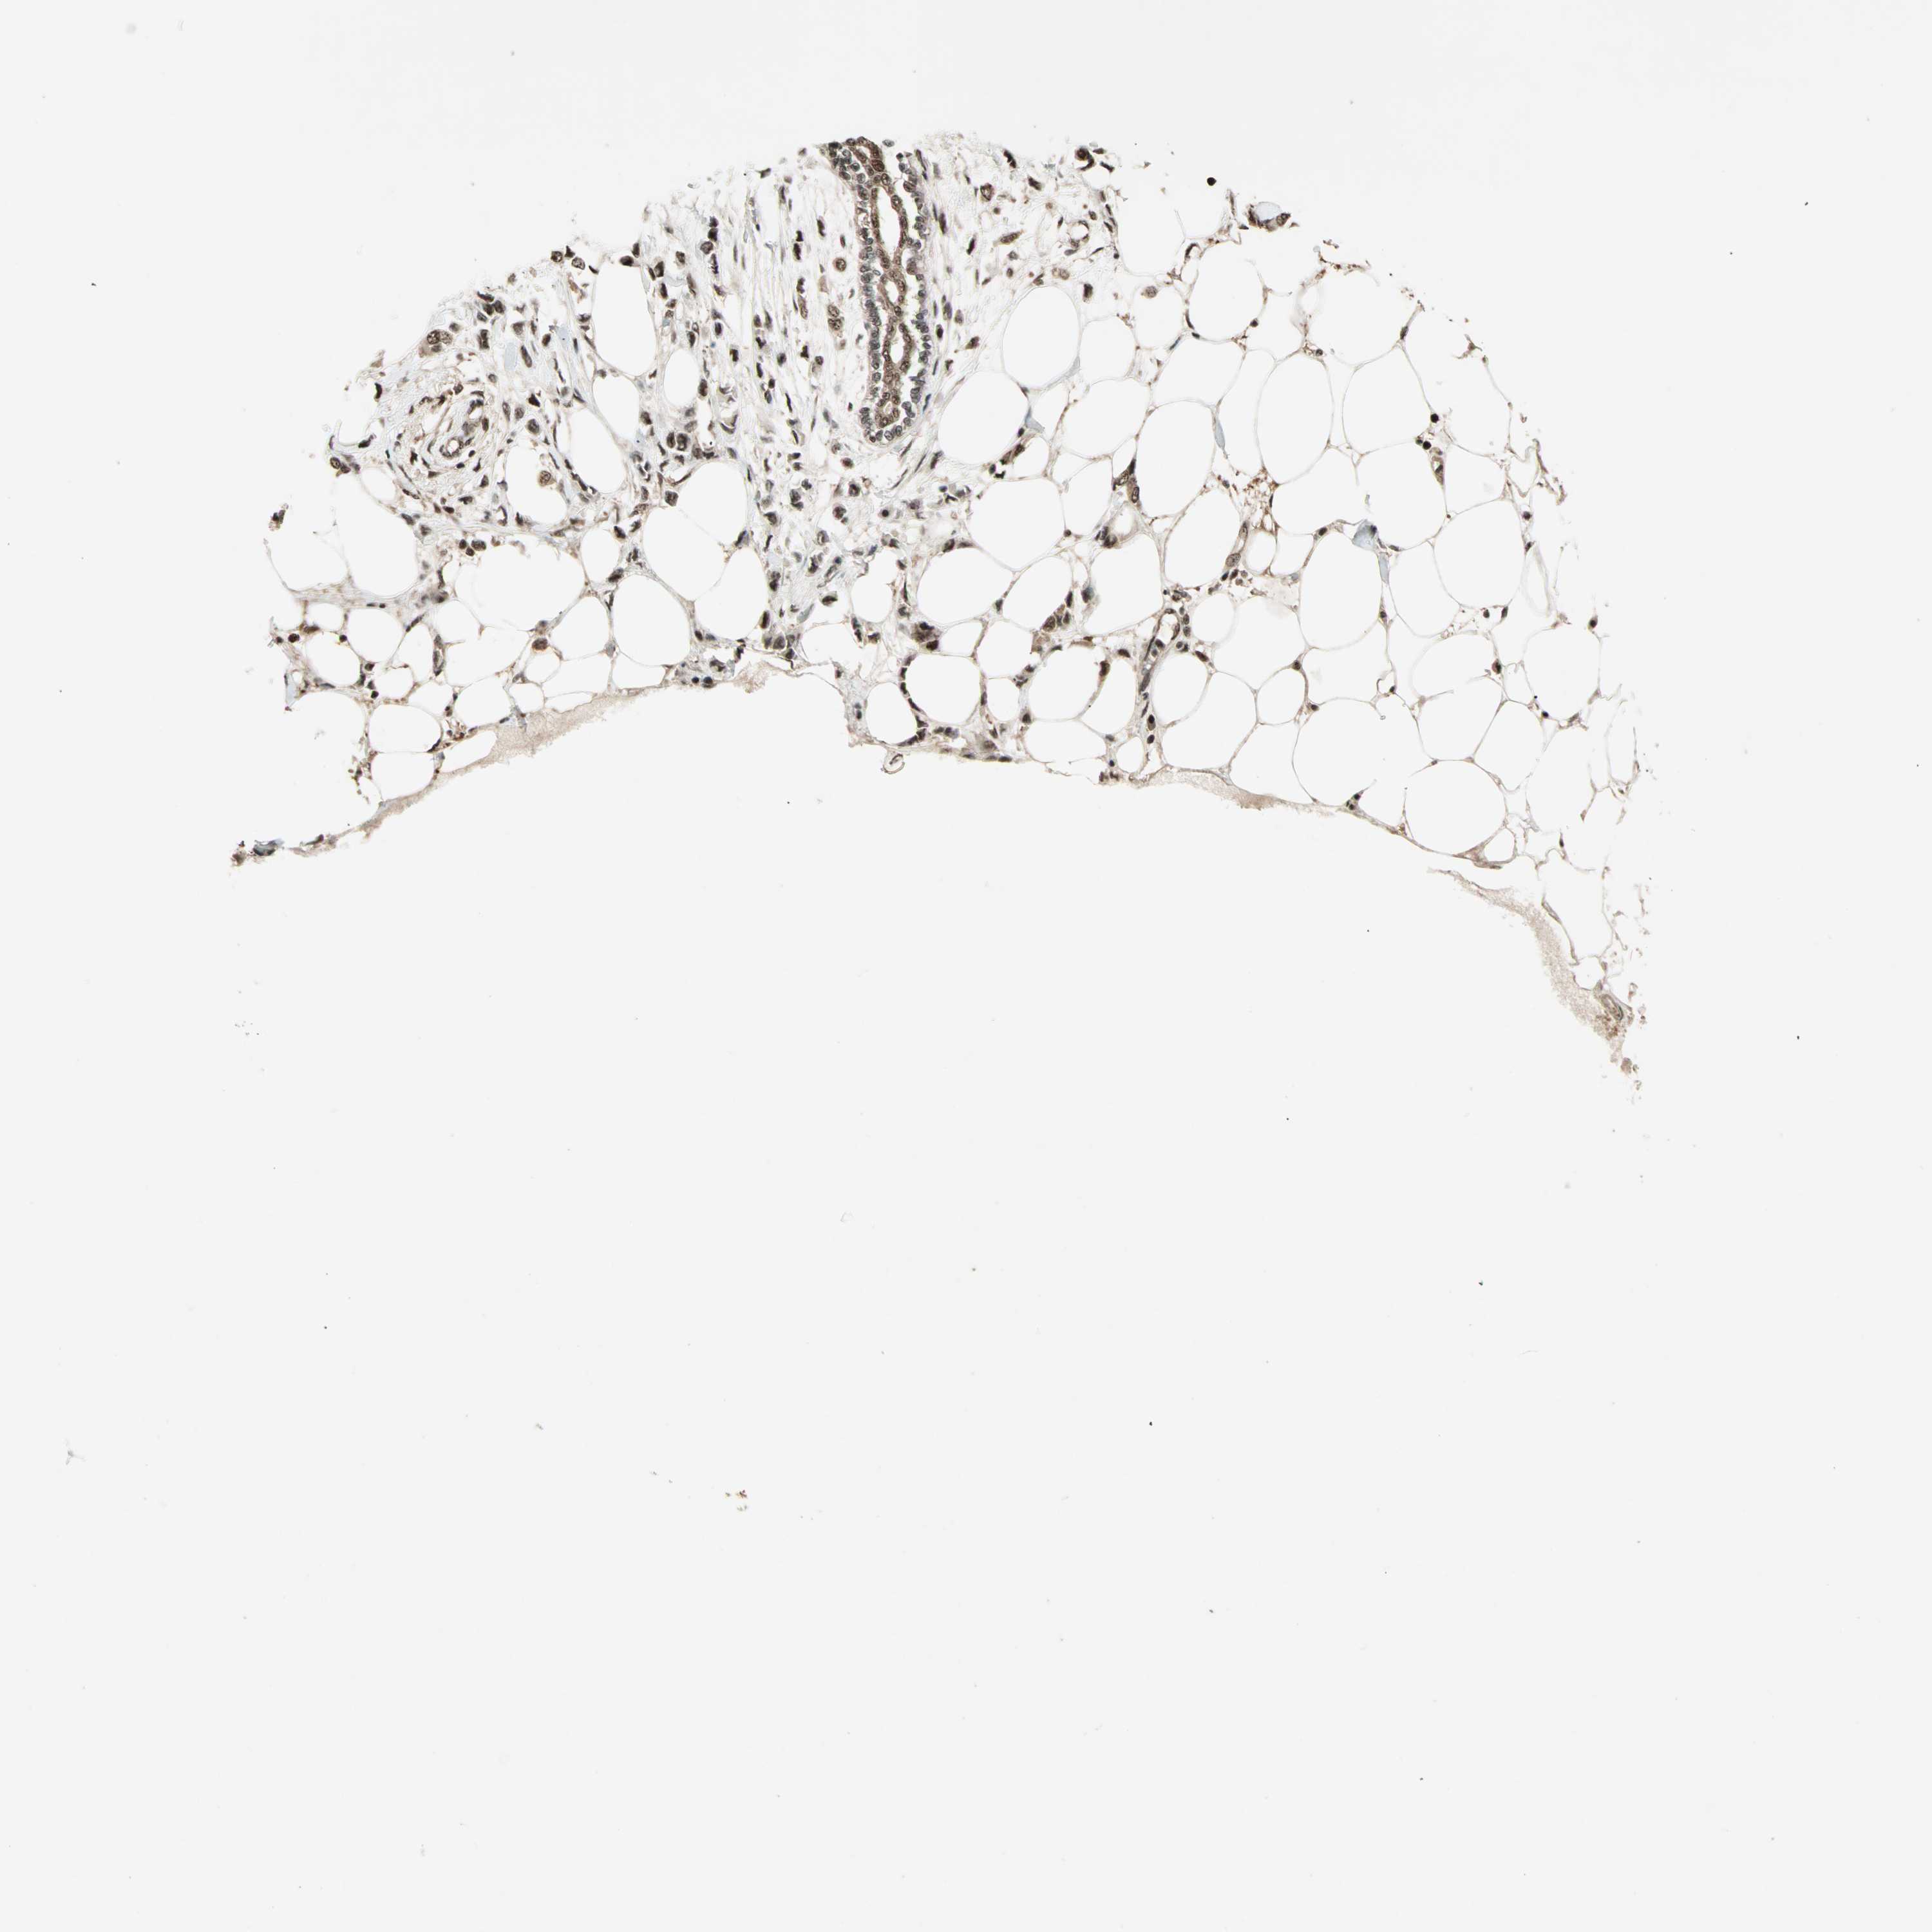

BRCA TCGA BRCA VALIDATION PROTEIN EXPRESSION

Breast cancer

Human cancer